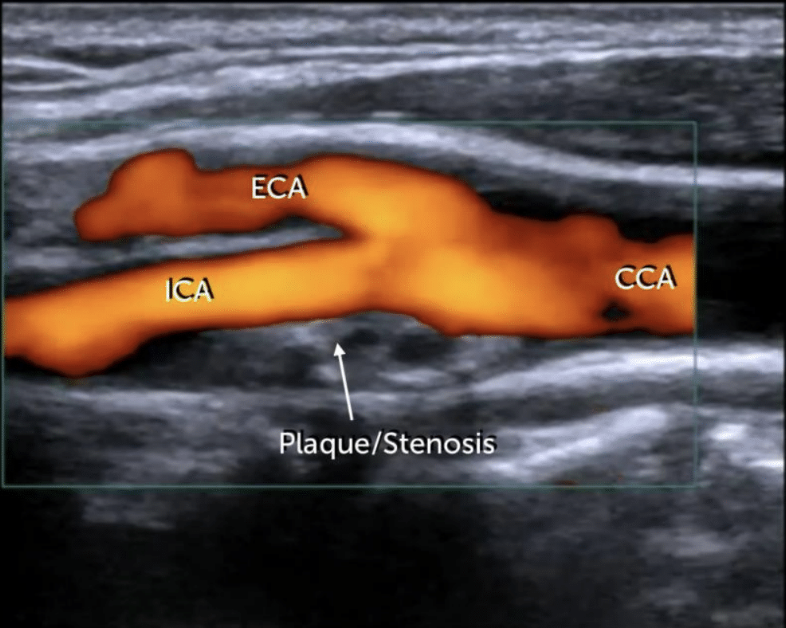

Hallazgos de doppler arterial

Placas de ateroma

Ausencia ed flujo

Cambios en la onda

Uso de doppler en carótidas

A

EVC

Vértigo

Síncope